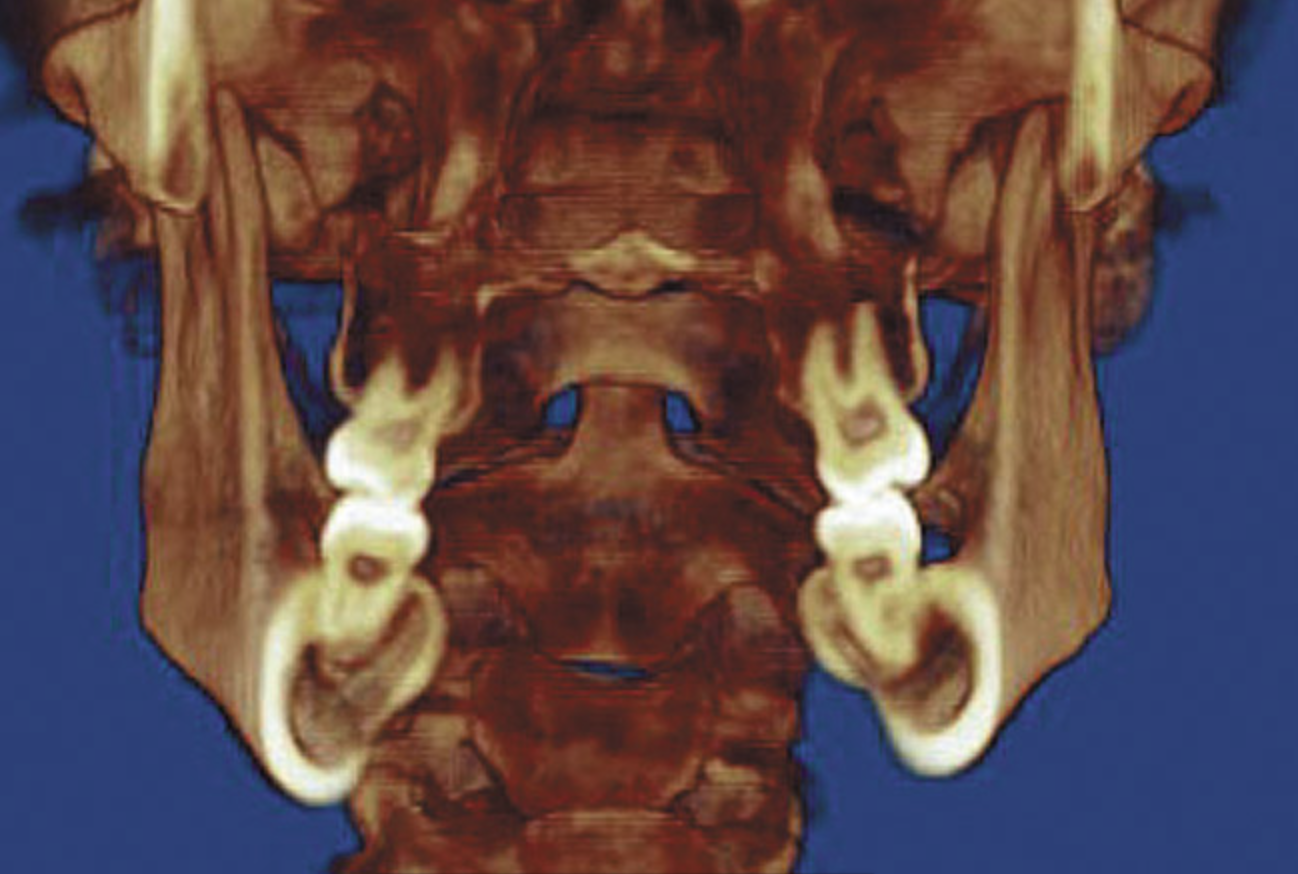

While most orthodontists appreciate anterior dental esthetics, some do not consider that the posterior teeth also have a normal alignment angle. The posterior teeth axial line angles appear to converge from the gingival through the occlusal toward a “central fulcrum.7 Alignment of teeth with significant crowding without extractions may cause a flaring of the axial alignment of both anterior and posterior teeth. If orthodontists do not extract teeth or reduce the width of teeth with interproximal reduction when the dental arch perimeter is greater than the skeletal arch perimeter, the teeth will be tipped, creating a “flared” appearance. Tipped teeth are not only esthetically unappealing, they are not centered in bone and do not allow occlusal forces to be directed down the long axis of the root, which impairs long-term stability (Figure 4). If treatment goals cannot be reached without extractions, then extractions must be considered.

Figure 4A  Coronal section of 3D tomograph revealing axial alignment of posterior teeth. A) Dental alignment does not allow occlusal forces to be directed down long axis of teeth. Maxillary teeth had been tipped to the buccal to compensate for the transverse discrepancy. B) Teeth are positioned to allow occlusal forces to be directed down long axis of teeth.

Figure 4A

Figure 4B  Coronal section of 3D tomograph revealing axial alignment of posterior teeth. A) Dental alignment does not allow occlusal forces to be directed down long axis of teeth. Maxillary teeth had been tipped to the buccal to compensate for the transverse discrepancy. B) Teeth are positioned to allow occlusal forces to be directed down long axis of teeth.

Figure 4B